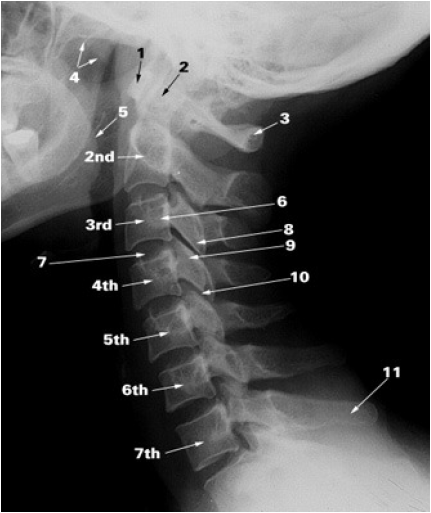

BIOMECHANICS OF HEAD MOTION

MOTION OF THE HEAD ON NECK

LATERAL TILT OCCURS BETWEEN C0-C1

ROTATION AT C1-2, FLEXION EXTENSION MAINLY AT C0-1

BIOMECHANICS OF NECK MOVEMENT

RANGE OF MOTION

BIOMECHANICS OF NECK MOTION

Most lateral flexion and flexion/extension occur serially from C2 through C7.

-

The majority of head rotation occurs at the atlanto-axial joint, so that muscles that act across this joint (e.g. obliquus capitis inferior, splenius capitis, SCM) have advantage in producing turning movements

- Rotation at C1-2 requires some extension and lateral tilt